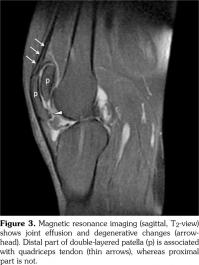

A 42-year-old male patient was examined due to gait difficulty and pain in hip and knee joints bilaterally and low back. He declared that he could walk independently, yet he had some difficulties in walking on undulating surfaces or climbing up stairs. Medical and family history was noncontributory. He was 168 cm tall and weighed 78 kg. Physical examination revealed severe restriction of range of motion in hip joints, crepitation in knee joints, hyperextension position of the first metacarpophalangeal joint, and deviation of the thumbs. Adam’s test for scoliosis was positive and lumbar motions were limited as well. Minimal joint effusion was detected in knee joints as well. Knee radiographies showed double- layered patella (DLP), generalized degenerative changes, scoliosis, and circumferential radiopaque lesion around the right hip joint (calcification of the iliopsoas bursa) (Figures 1 and 2). Magnetic resonance imaging designated the association between the quadriceps tendon and patella (Figure 3). Laboratory investigations including erythrocyte sedimentation rate and C-reactive protein, calcium, phosphate, and alkaline phosphatase levels were all within normal limits. Overall, the patient was diagnosed with secondary OA due to MED and referred to another center for further genetic analysis. A written informed consent was obtained from the patient.

Our patient with clunking in the knees had DLP bilaterally, which was reported previously in the literature.(8) DLP is a type of bipartite patella and caused by a septum dividing the patella into segments. It can be seen completely or partially. In general, DLP is associated with MED; however, it is reported in nondysplastic subjects as well.(9) Our patient had the total form of DLP. Magnetic resonance imaging showed that the distal part of the DLP was responsible for the extensor mechanism of the knees. This condition is important because the functional part could be indicative for a possible surgical procedure or functionality of the knee movements.